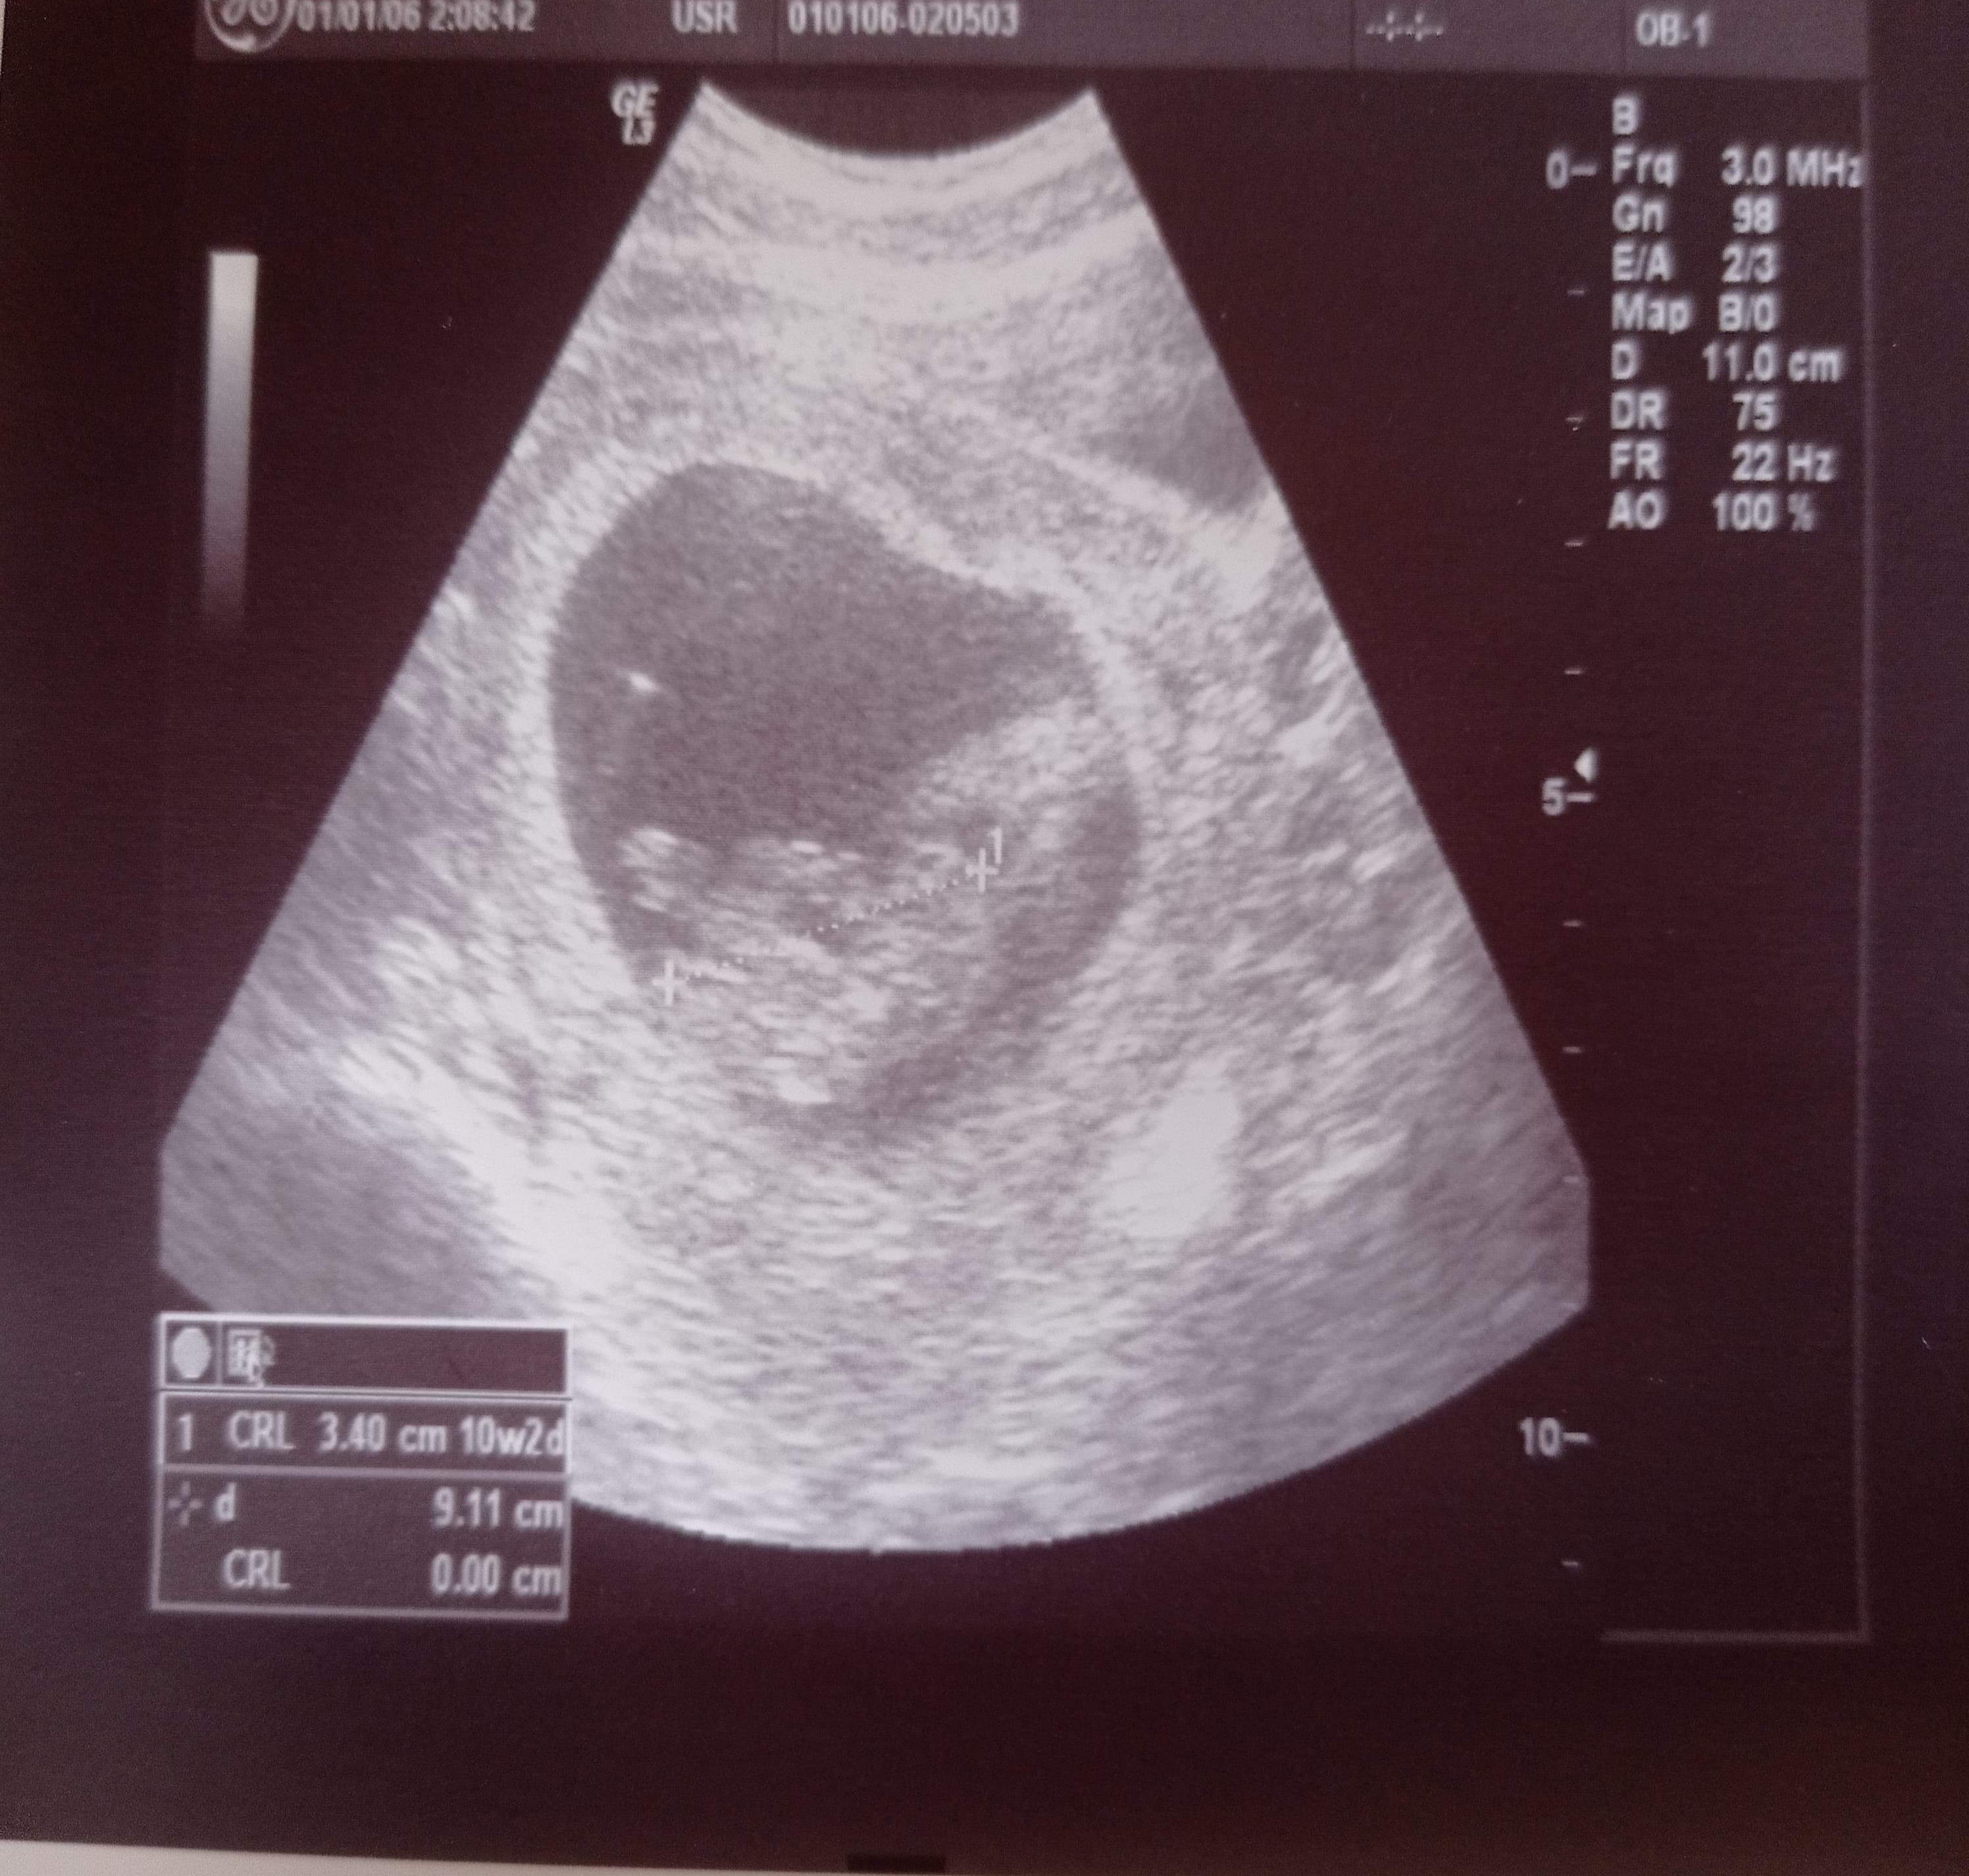

Witam,ostatnia miesiączkę miałam 11.12 cykle zazwyczaj 34-36 dni. moja pani ginekolog ma sprzęt z ery kamienia łupanego nie potrafiła zmierzyć dzidziusia.. w końcu jak się udało doszła do wniosku, że dzidziuś jest młodszy niż wychodzi z OM.. 25.02 miałam USG wymiary 3,40cm 10w2d. Czy mam zmienić lekarza, który ma lepszy sprzęt i nie będę musiała się domyślać czy wszystko jest ok i czy się nie myli ?

Też bym zmieniła. Jednak obraz USG jest ważny, nie tylko do określenia wieku ciąży, ale przede wszystkim do sprawdzenia czy z dzieckiem wszystko ok, czy rozwija się prawidłowo.

Dla Ciebie niepotrzebny stres, a jednak dobre USG pozwoli wykryć szybciej ewentualne nieprawidłowości.